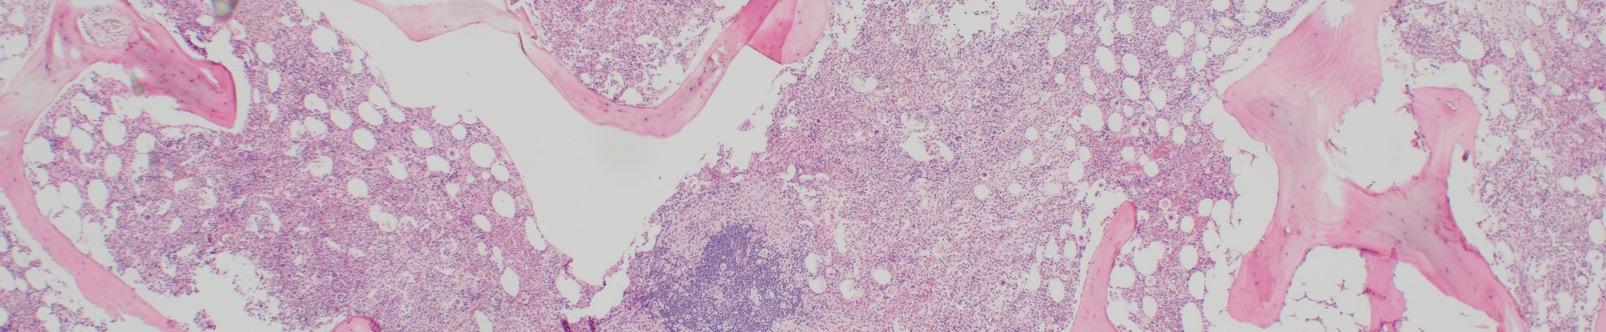

BM aspirate

Images courtesy of Tracy George, MD, and Anton Rets, MD, PhD.